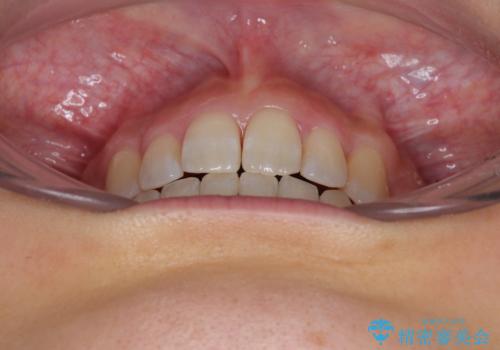

八重歯を改善 ワイヤー装置での抜歯矯正

八重歯をスムーズに解消するために、補助装置を用いることで速やかに歯列を整えることができました。